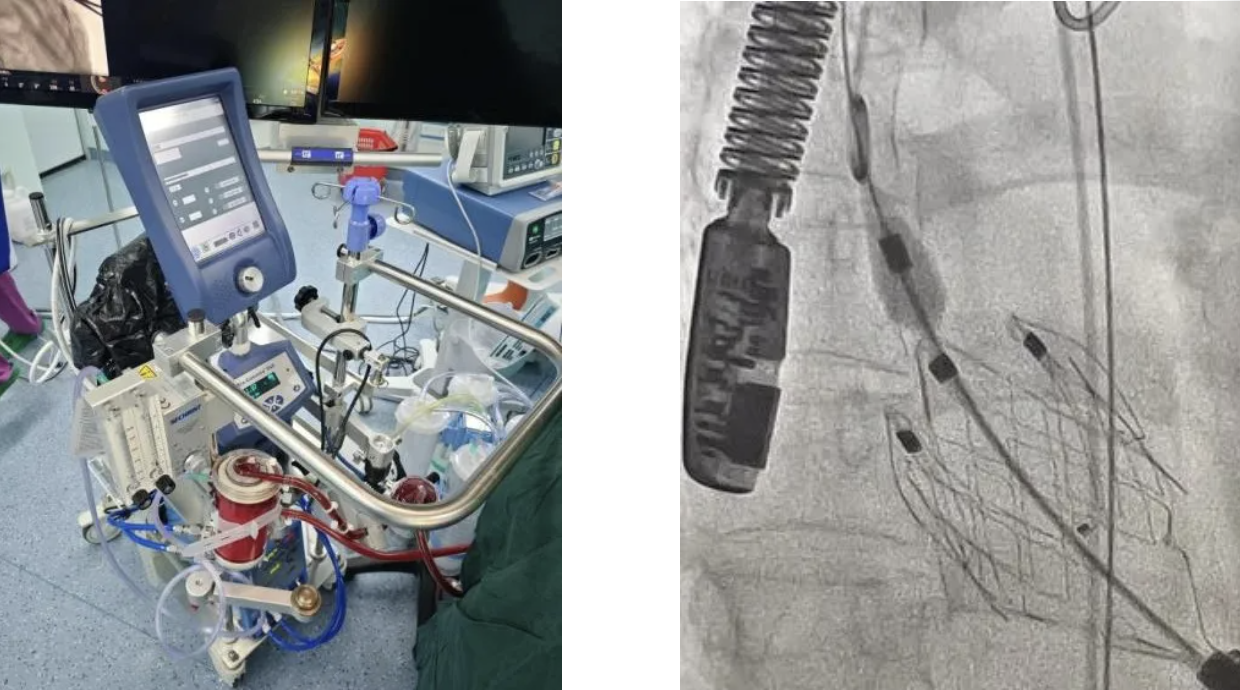

面对这一棘手的难题,西安市第三医院心脏血管外科团队迅速行动,联合麻醉科、超声科、影像科、重症医学科等多学科专家展开紧急会诊。经过深入讨论和综合评估,最终决定采用经心尖 TAVR 技术。这是一种无需开胸、无需体外循环的微创瓣膜置换术,并且将在 ECMO(人工心肺)的支持下为手术保驾护航。

手术过程中,医生仅在患者左侧肋间切开一个 3 - 4 厘米的小口,通过心尖将人工瓣膜精准地送入病变位置,成功替换掉“失灵”的主动脉瓣。整个手术过程中心脏保持跳动状态,最大程度地保护了患者脆弱的心功能。